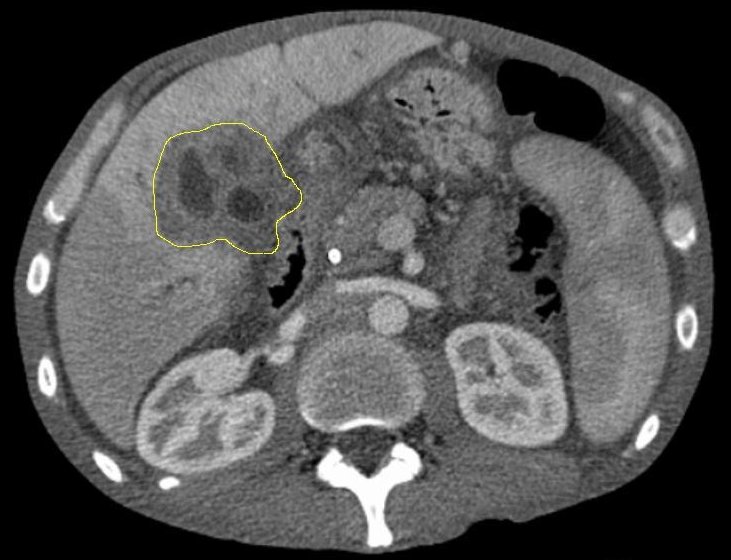

Bildquelle: Originalautor en:User:Samir, CT cholangioca-mark, (CC BY-SA 3.0)

Gallengangskarzinom: Herausforderung Früherkennung